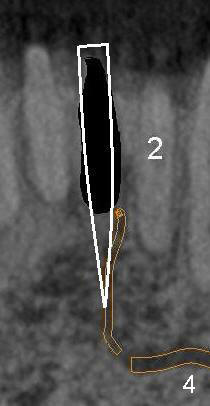

After extraction of the central (Fig.3 black area), osteotomy for an immediate implant (Fig.4 white outline) should have a chance to violate the integrity of the terminal segment of the incisive canal, causing hemorrhage. Once the implant is placed, the hemorrhage should be able to stop.